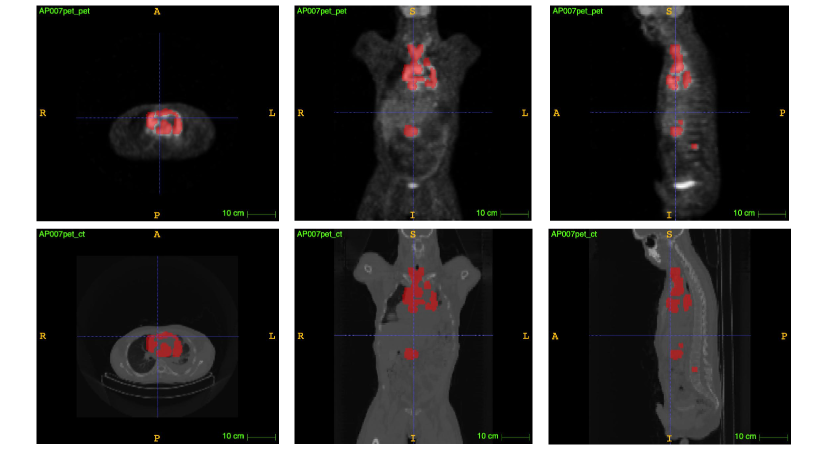

Fig. 5 shows an example of segmentation results obtained by ES-UNet. Our model can locate and segment most of the lymphomas. The segmentation results were found credible and were confirmed by experts.

Refer to caption

Figure 5: Segmentation results of ES-UNet. From left to right: ground truth, segmentation results, difference map between the ground truth, and segmented lymphomas.